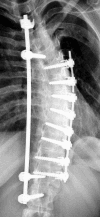

Background: Spinal fusion surgery is currently recommended when curve magnitude exceeds 40-45 degrees. Early attempts at spinal fusion surgery which were aimed to leave the patients with a mild residual deformity, failed to meet such expectations. These aims have since been revised to the more modest goals of preventing progression, restoring 'acceptability' of the clinical deformity and reducing curvature.In view of the fact that there is no evidence that health related signs and symptoms of scoliosis can be altered by spinal fusion in the long-term, a clear medical indication for this treatment cannot be derived. Knowledge concerning the rate of complications of scoliosis surgery may enable us to establish a cost/benefit relation of this intervention and to improve the standard of the information and advice given to patients. It is also hoped that this study will help to answer questions in relation to the limiting choice between the risks of surgery and the "wait and see - observation only until surgery might be recommended", strategy widely used. The purpose of this review is to present the actual data available on the rate of complications in scoliosis surgery.

Conclusion: Scoliosis surgery has a varying but high rate of complications. A medical indication for this treatment cannot be established in view of the lack of evidence. The rate of complications may even be higher than reported. Long-term risks of scoliosis surgery have not yet been reported upon in research. Mandatory reporting for all spinal implants in a standardized way using a spreadsheet list of all recognised complications to reveal a 2-year, 5-year, 10-year and 20-year rate of complications should be established. Trials with untreated control groups in the field of scoliosis raise ethical issues, as the control group could be exposed to the risks of undergoing such surgery.